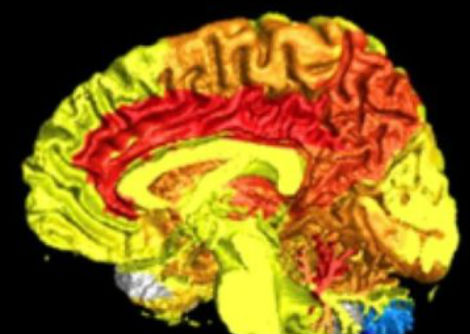

وفي عام 2025 أضافت لجنة نوبل فصلًا جديدًا إلى هذا التاريخ المجيد، إذ منحت جائزة نوبل في الطب لثلاثة علماءٍ أسهموا في كشف أسرار "التسامح المناعي المحيطي" — تلك الآلية الدقيقة التي تحفظ توازن جهاز المناعة بين الدفاع عن الجسم ومنع مهاجمة أنسجته الذاتية. كان هذا الاكتشاف ثمرة عقودٍ من البحث والتجريب، ومثّل تحوّلًا جذريًّا في فهم الطب الحديث لأصل الأمراض المناعية الذاتية. وقد جاء هذا الإنجاز تتويجًا لأعمال فريد رامزدل وشيمون ساكاجوتشي وماري برونكاو الذين كُرِّموا على إسهامهم في حل أحد أكثر ألغاز جهاز المناعة تعقيدًا، وهو كيف يستطيع هذا النظام المعقّد أن يدافع عن الجسم ضد الفيروسات والبكتيريا والخلايا السرطانية من غير أن ينقلب على نفسه ويدمّر خلاياه السليمة.